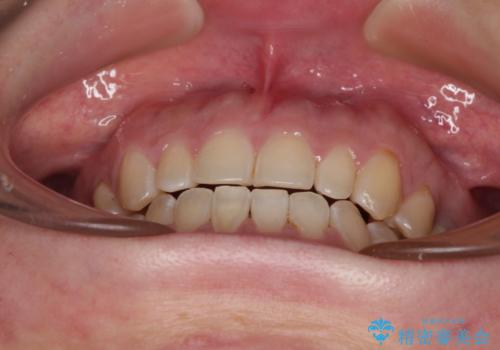

舌の突出癖改善のトレーニングが全くうまくできず、治療期間が長期化しました。

早く治療を終えたいとの要望があり、トレーニング次第と伝えるとようやく練習をするようになり、その後は速やかに上下の隙間が改善されました。